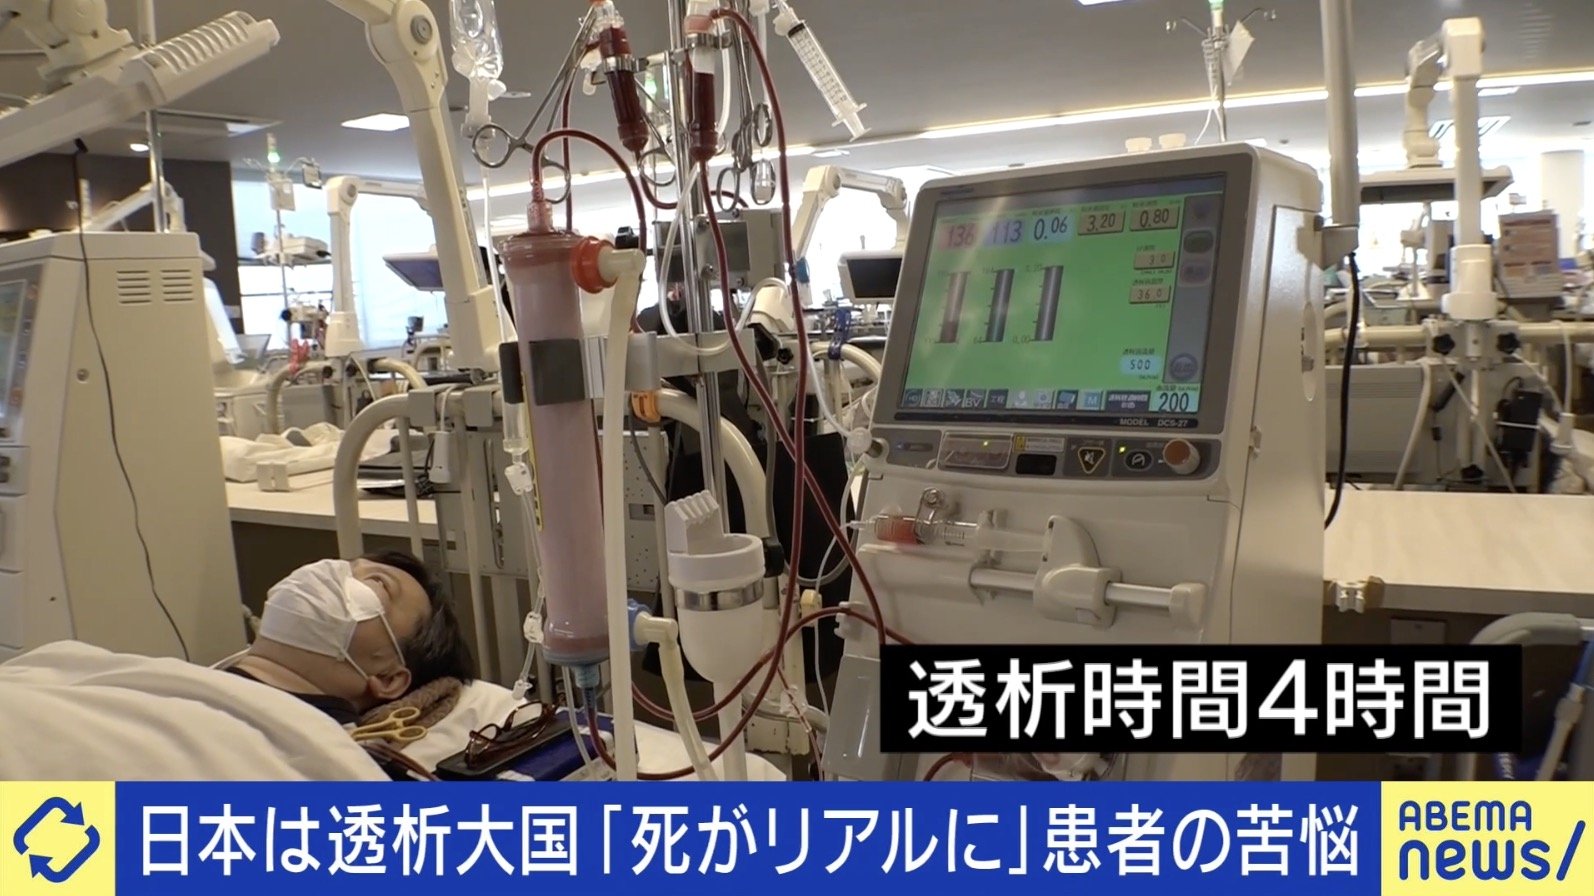

jmedmook96 歩いてくるレッドフラッグ もう困らない外科系当直 | 日本医事新報社 W, 2ページ目) 「命をつなぐ行為」 “透析大国”日本、一方で進まない患者への理解 「“輸血に使われたくないから献血しない”という誤った知識も…」 | 国内 | ABEMA TIMES | アベマタイムズ,

2ページ目) 「命をつなぐ行為」 “透析大国”日本、一方で進まない患者への理解 「“輸血に使われたくないから献血しない”という誤った知識も…」 | 国内 | ABEMA TIMES | アベマタイムズ, 朝倉書店『内科学』(第12版)デジタル付録,